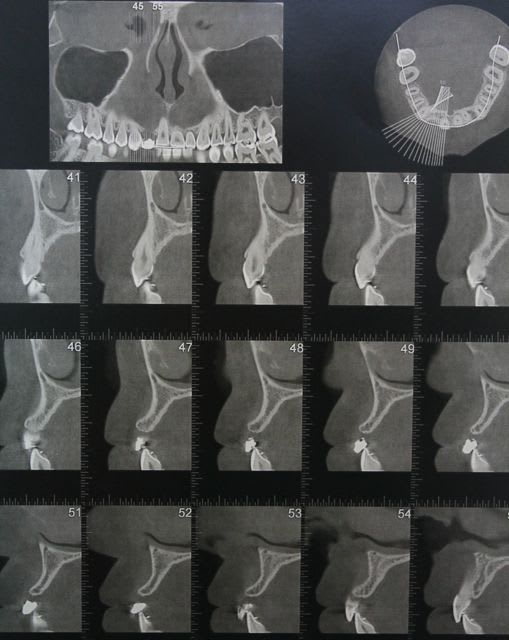

la suite et le début:

scan pré op: pas bcp d'os dispo au niveau de 46 47, y'a fallu aller plus loin derrière

la 11: voir son axe et le peu d'os autour en vestibulaire

photo de la cica à quelque mois

bientôt scan et pose de l'implant